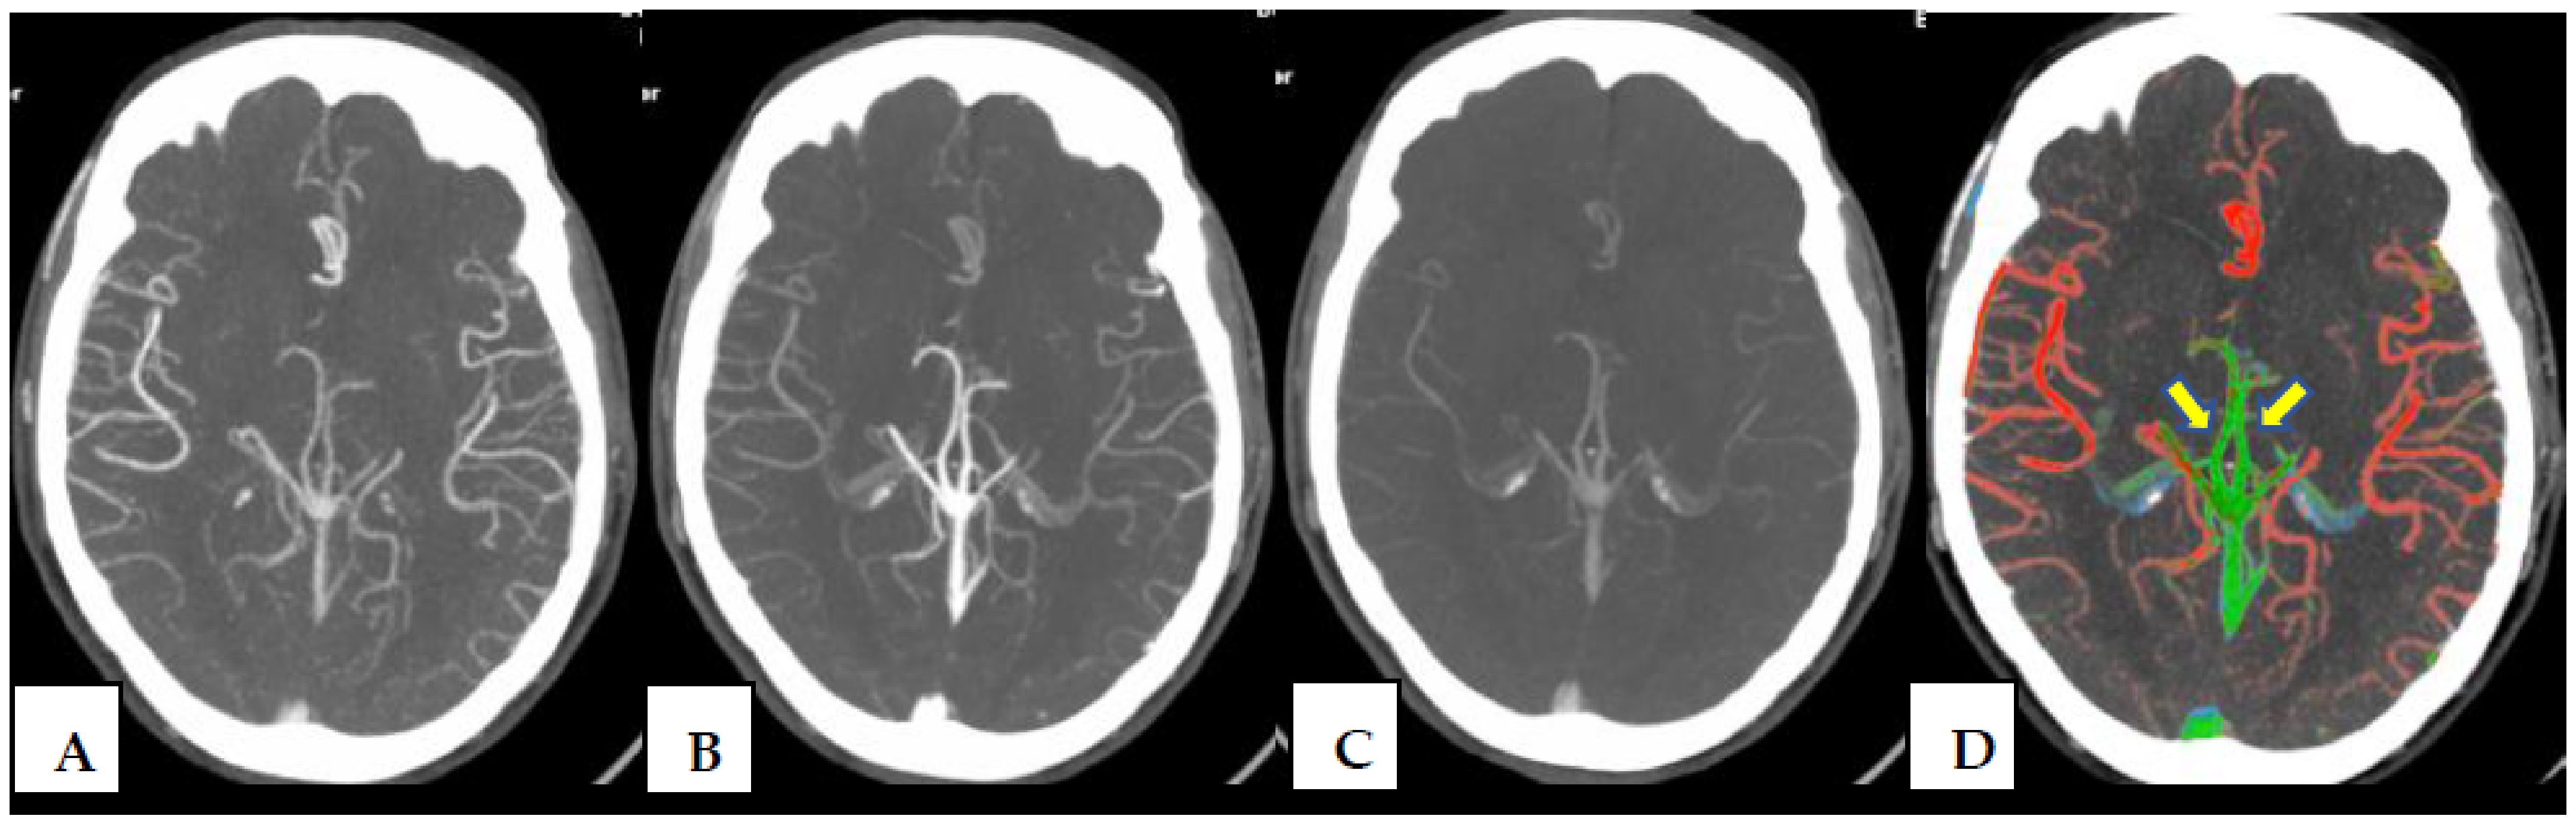

Evaluation of Intracranial Arteriovenous Malformations Using Ischemic Stroke Color-Coded Maps Software, a New Rapid Post-Processing Tool in CT Angiography

2.2. CT Protocol and Post-Processing Tool

| ColorViz—Assessment of AVM Components | |

| Nidus Presence | Yes/No |

| Nidus type | Compact/Diffuse |

| Arterial feeder | Single/Multiple |

| Venous sinus color asymmetry | Yes/No |

| Venous drainage | Superficial veins/Deep veins/Both |